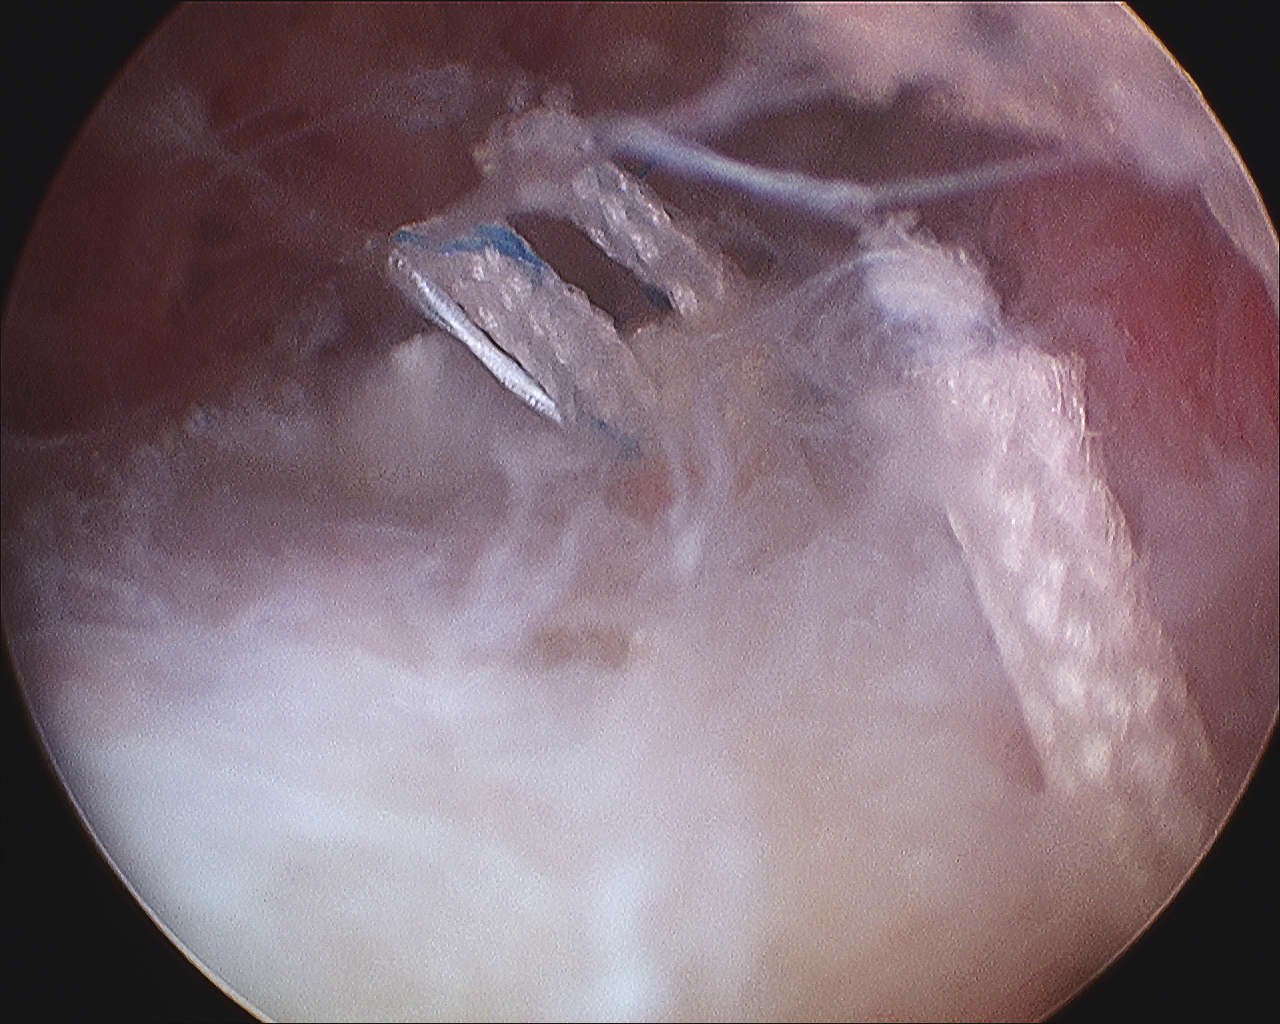

> 50% uncovering of footprint in glenohumeral joint